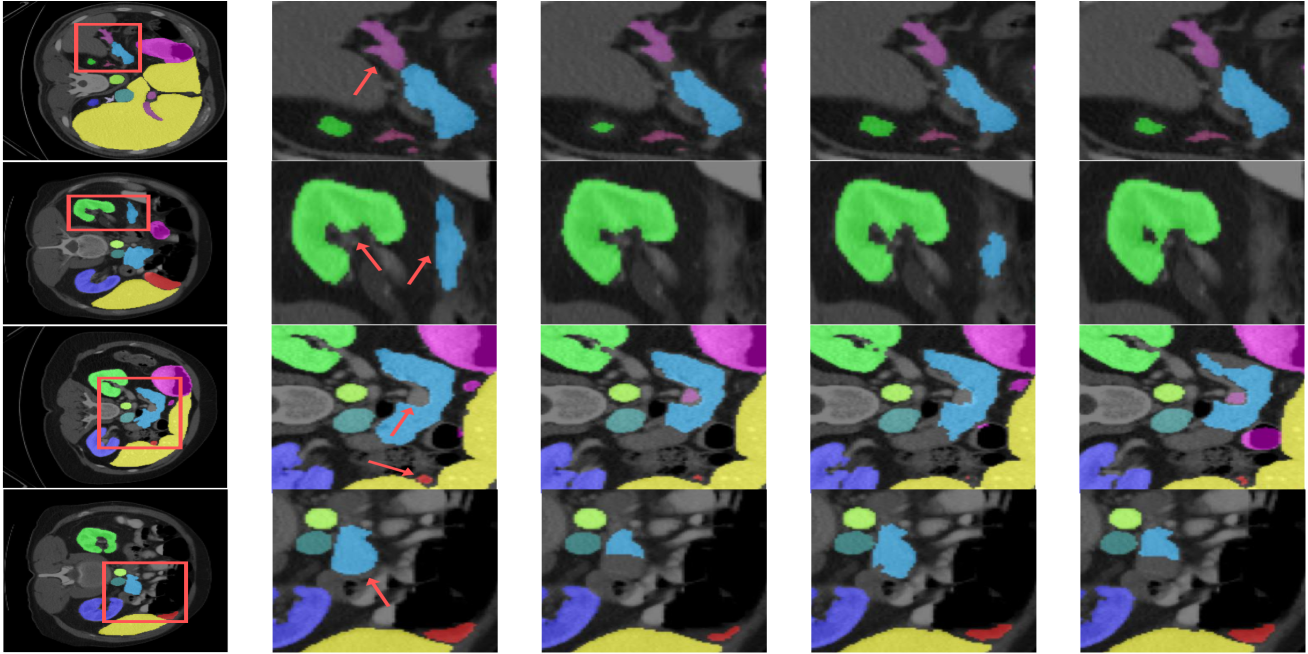

Refer to caption

Figure 5: Qualitative results of the proposed model. The region of interest was highlighted with arrows. (From left: GroundTruth, DTS(our), UNet, SwinUNETR, Diff-UNet)

6 Comparative Results

As shown in Table.6, we compare our model with the BTCV benchmark dataset. Compared with other models, the proposed DTS achieves the best performance and presents a higher dice result of 0.906. It can be seen that previous diffusion segmentation models show comparable performance to conventional segmentation models in relatively large organs(e.g. liver, stomach), but poor performance in small organs(e.g. esophagus, aorta). DTS surpasses the closest competing methods by an average of 2% across all classes, with an even more significant improvement of 7% specifically for gall bladder. We believe that our approach and the application of the high performance transformer architecture will lead to improved accuracy. Comprehensive qualitative results of our model, which demonstrate good segmentation performance for small organs, can be found in Fig.5, highlighting our model’s ability to capture details and achieve accurate boundary representations.